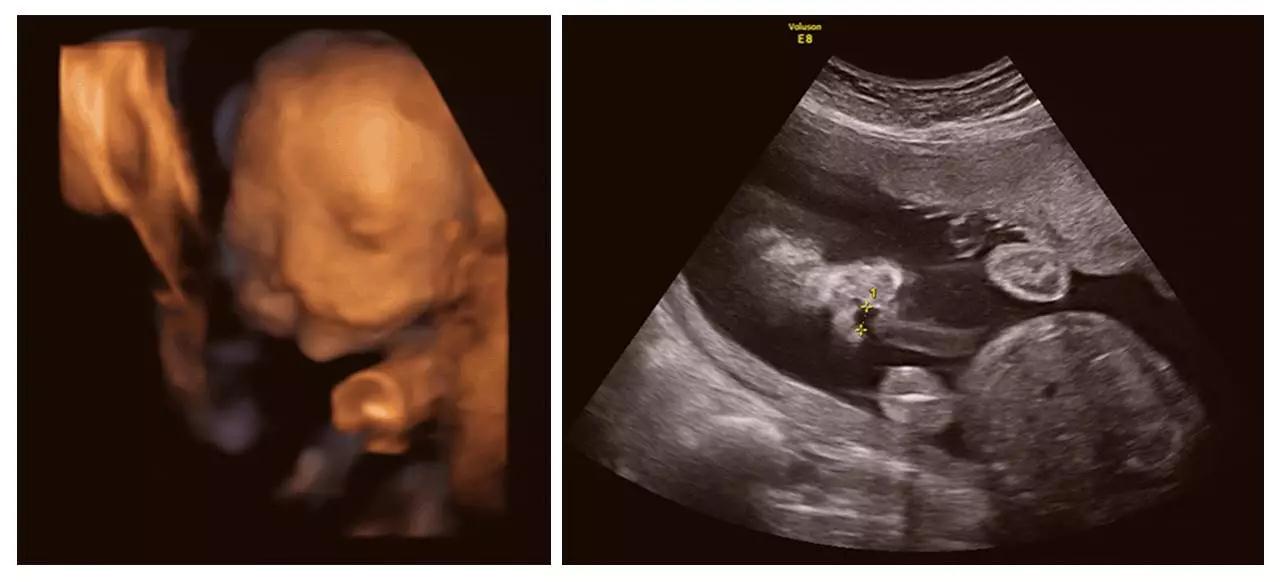

(单侧唇裂)

(双侧唇裂)